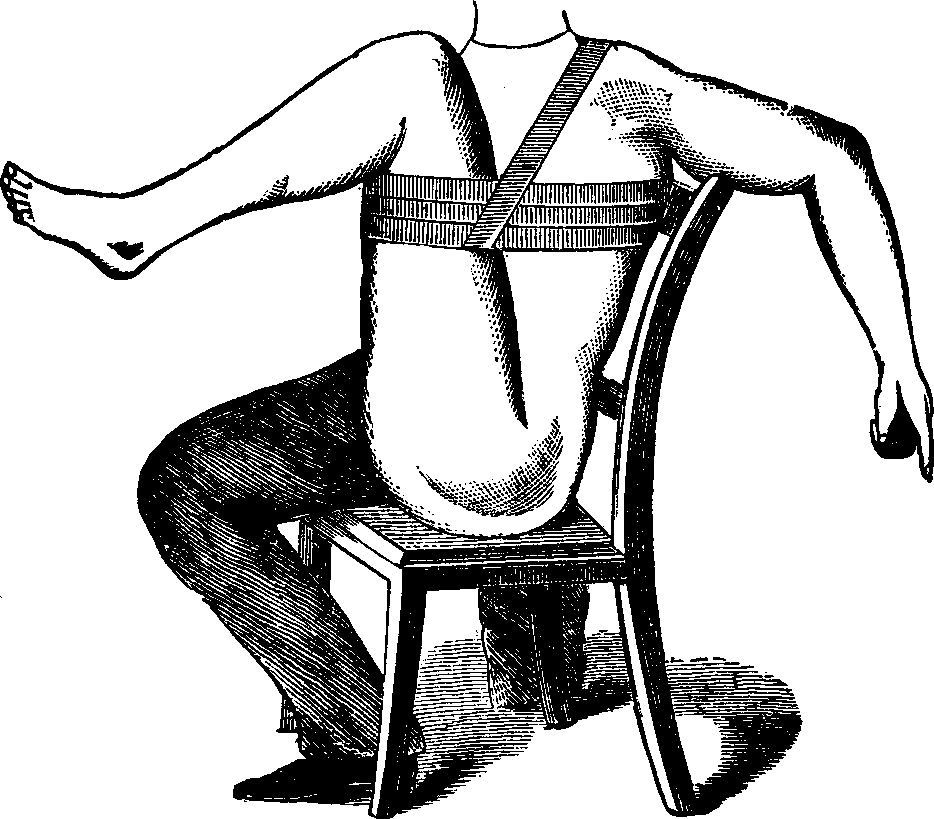

Fig. 3. THE UTERINE DILATOR. This instrument is introduced

into the canal of the uterine neck with its blades closed. By means of the

thumb-screw the blades are then separated as shown in this illustration,

the cervical canal being thereby dilated to the required extent.

Treatment. From the nature of this malady, it will readily be seen that no medical treatment can effect a radical cure. We must therefore resort to surgery. In a small proportion of cases, the stricture may be cured by repeated dilations of the constricted part of the cervical canal. This may be accomplished by using a very smooth probe which is fine at the point, but increases in size, so that its introduction will widen and expand the orifice and canal. The stricture may be overcome in many cases by using different sized probes. In some instances, we have employed the uterine dilator, represented by Fig. 3. We have also introduced sea-tangle and sponge tents into the neck of the womb, and allowed them to remain until they expanded by absorbing moisture from the surrounding tissues. The latter process is simple, and in many cases preferable. By means of a speculum (see Figs. 15 and 16), the mouth of the womb is brought into view, and the surgeon seizes a small tent with a pair of forceps and gently presses it into the neck of the womb, where it is left to expand and thus dilate the passage. If there seems to be a persistent disposition of the circular fibers of the cervix to contract, and thus close the canal, a surgical operation will be necessary to insure permanent relief. In performing this operation, we use a cutting instrument called the hysterotome (see Figs. 4 and 5). By the use of this instrument, the cervical canal is enlarged by an incision on either side. The operation is but slightly painful, and, in the hands of a competent surgeon, is perfectly safe. We have operated in a very large number of cases and have never known any alarming or dangerous symptoms to result. After the incision, a small roll of cotton, thoroughly saturated with glycerine, is applied to the incised parts, and a larger roll is introduced into the vagina. The second day after the operation, the cotton is removed, the edges of the wound separated by a uterine sound or probe, and a cotton tent introduced into the cervix, and allowed to remain, so that it will expand and thus open the wound to its full extent. This treatment must be thoroughly applied, and repeated every alternate day, until the incised parts are perfectly healed.